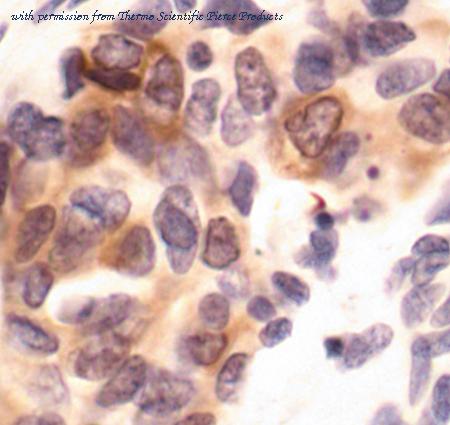

application: Western blot, immunohistochimie, immunohistochemistry - paraffin section

- prkcq anticorps